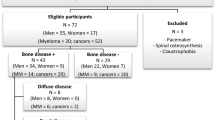

Fifty PCa patients at high risk for metastasis were enrolled (50 men; mean age, 67 ± 10 years; range, 59–87 years). Forty patients had newly diagnosed disease with high risk of metastasis based on a Gleason score ≥ 8 and/or ≥ 20 ng/ml PSA; 10 patients had PSA recurrence with a PSA doubling time ≤ 12 months after radical treatment or were receiving androgen-deprivation therapy. According to the reference standard, 38 of 50 patients (76%) had bone metastases (Fig. 1). Of these 38 patients, 34 (89.5%) had focal lesions and 4 (10.5%) had diffuse bone marrow involvement.

Forty-seven patients with histologically proven, newly diagnosed MM were enrolled (27 women and 20 men; mean age, 62.5 ± 9 years; range, 47–90 years). According to the reference standard, 31 of 47 patients (66%) had bone marrow involvement on MRI (Fig. 2). Among these patients, 23 (74%) had focal lesions, 5 (16%) had diffuse bone marrow involvement, and 3 (10%) had a salt-and-pepper pattern.